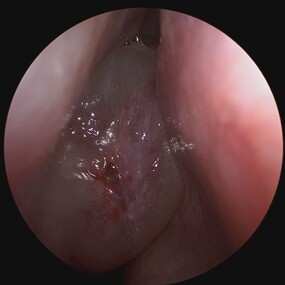

Sinus Pathology

Sino-Nasal Polyps

Sino-Nasal Polyps are non-cancerous growths that develop in the lining of the nose or sinuses. They can obstruct the nasal passages and sinuses, leading to symptoms similar to chronic sinusitis such as nasal congestion, facial pressure, and reduced sense of smell.